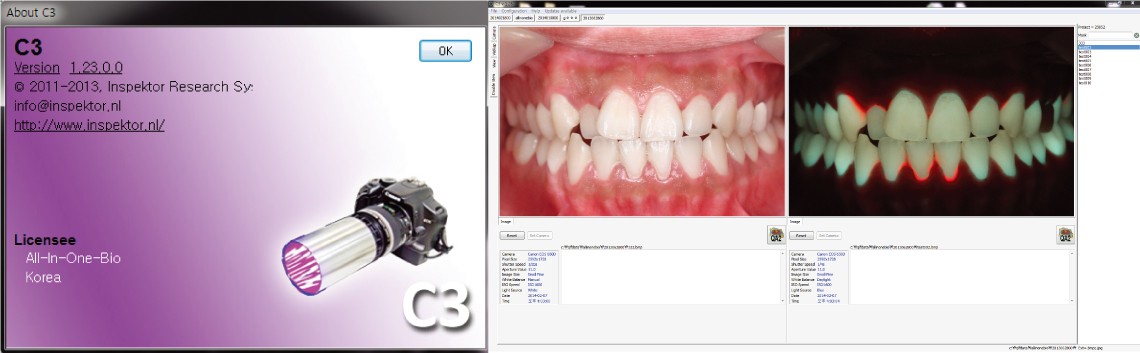

QLF-D촬영프로그램(C3)

큐레이를 사용하여 구강 내 세균 등을 촬영하고 촬영된 이미지를 확인하는 뷰어 프로그램입니다.